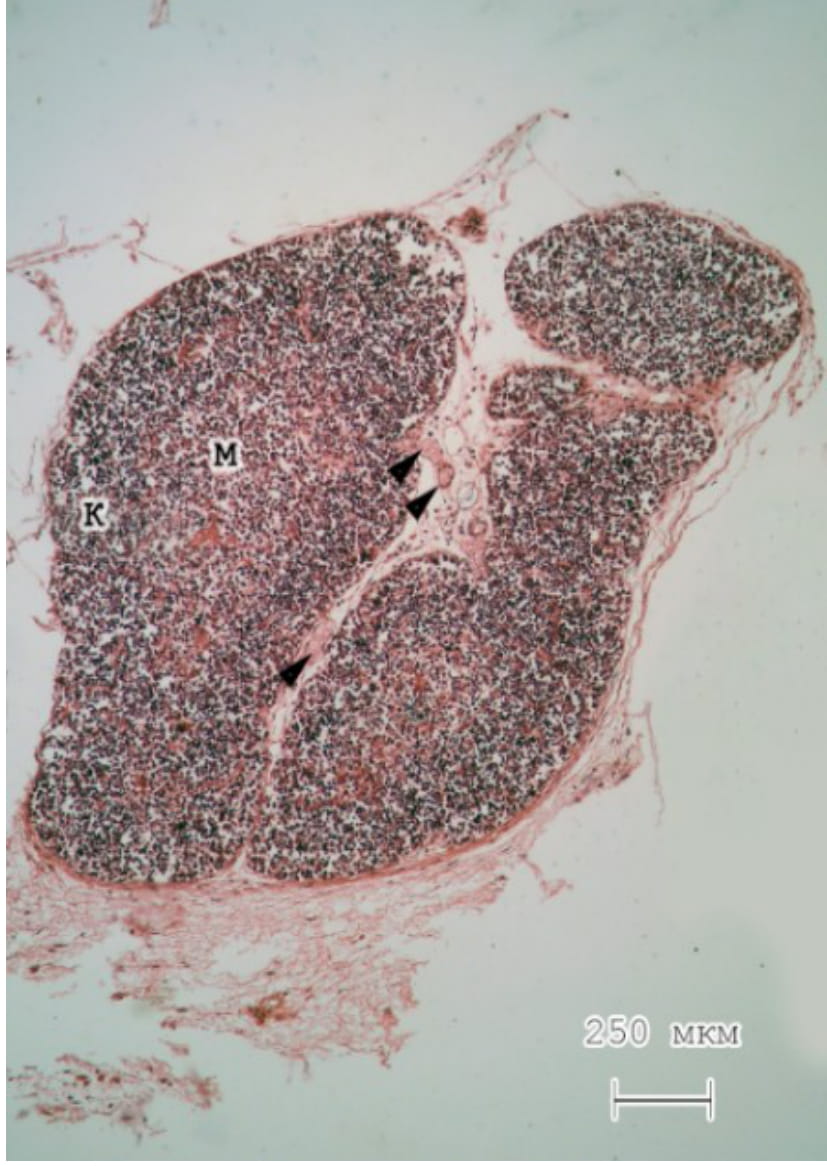

При гистологическом исследовании на малом увеличении видно, что дольки тимуса имеют овальную форму. Количество септ незначительно. В пределах последних, а также между долями тимуса, хорошо определяются сосуды и небольшое количество жировой ткани. Исследование на светооптическом уровне тимуса крыс обеих групп показало, что граница между корковым и мозговым веществом плохо выражена. При этом все же видно, что центр долек окрашивается менее интенсивно в сравнении с их периферическими отделами (рис. 1, 2).

Рис. 1. Тимус новорожденной крысы контрольной группы. Объектив – х4. Гематоксилин и эозин

Примечания: граница между корковым и мозговым веществом определяется не четко; К – корковое вещество; М – мозговое вещество